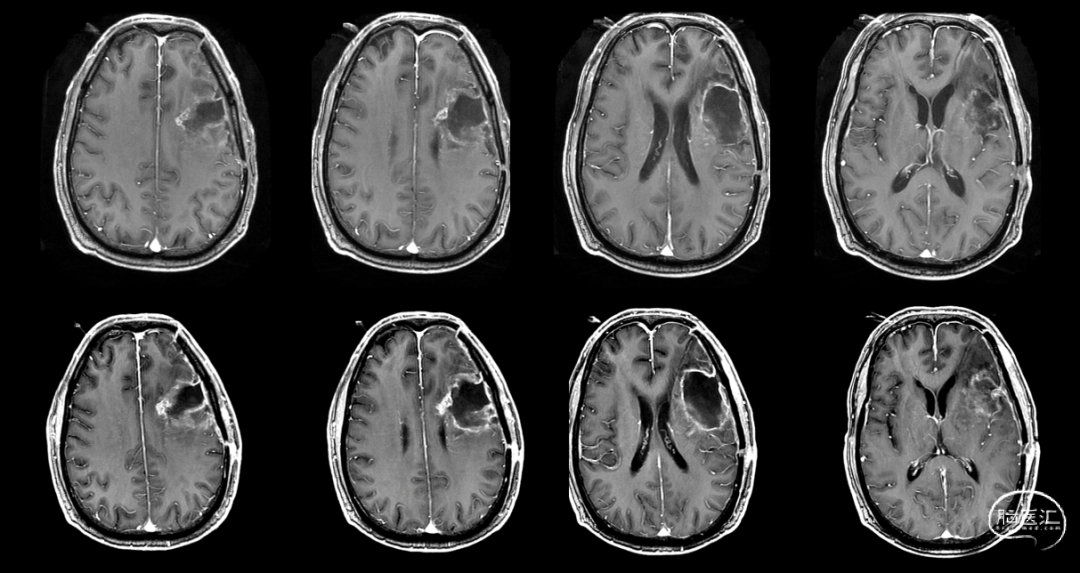

肿瘤电场治疗16天,RT后1月(2020-07-22):图示。

放疗后8月(2021-03-17):如视频和图像。

术后5周开始实施标准的新STUPP方案的辅助治疗,即在同步放化疗后,辅助替莫唑胺化疗的同时使用了电场治疗。目前生存25月,且临床和影像学表现均提示稳定,未见复发迹象。期间,在放疗后7月时复查MRI提示异常FLAIR信号区增大,经我院MDT讨论,考虑到强化信号减轻,无明显占位效应,患者无症状体征,考虑是治疗后水肿,非进展,故继续按原方案治疗。放疗后17月复查MRI出现术区边缘局部强化范围稍增大,但PWI示强化区局部呈低灌注且未见弥散受限表现,MDT讨论考虑为假性进展,继续原方案治疗。后续复查MRI强化范围减轻,证实了MDT的判断证实疾病稳定。患者生存时间已达25个月。全程安全顺利,仅出现一过性轻度皮肤反应。

辅助TMZ治疗过程中每2-3月复查MRI。治疗中曾出现水肿范围增大,尽管有部分区域弥散受限和MRS异常及血流量增加,但是临床症状未加重,仍继续原方案治疗,后续监测PWI显示病变区灌注减低。提示持续肿瘤电场治疗可以使病变长期稳定。此患者每天佩戴肿瘤电场治疗时间接近22小时,中间出现头皮发红和小水泡,经局部外用皮质类固醇和外用抗生素,暂停2天治疗恢复。至今随访25月稳定。说明肿瘤电场治疗联合TMZ治疗较单TMZ治疗明显延长胶质母细胞瘤患者PFS及OS,临床应积极推广使用。